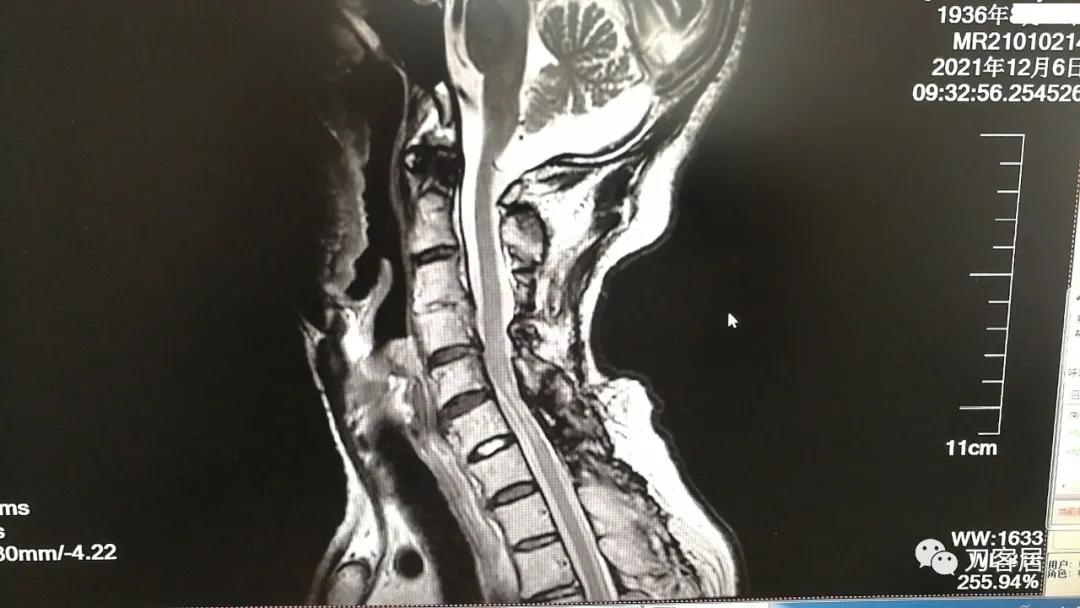

图23. 2021年12月6日复查颈椎MRI-2,提示颈5-7平面椎管狭窄,脊髓动态受压,脊髓信号改变。

图24. 2021年12月6日复查颈椎MRI-2,提示颈5-7平面椎管狭窄,脊髓动态受压,脊髓信号改变。片子显示患者为1936年生,那么现在的年龄应该是接近86岁了。

从这两张颈椎MRI片子来看,颈3-4椎体分节不全,颈2-5椎管成形手术减压很好,椎管无狭窄,脊髓后移,颈5-7椎管有狭窄,脊髓信号改变。此信号改变可能系脊髓萎缩,也可能是头段脊髓后移后,颈5-6节段后方椎板仍在,椎管相对狭窄,脊髓受压。